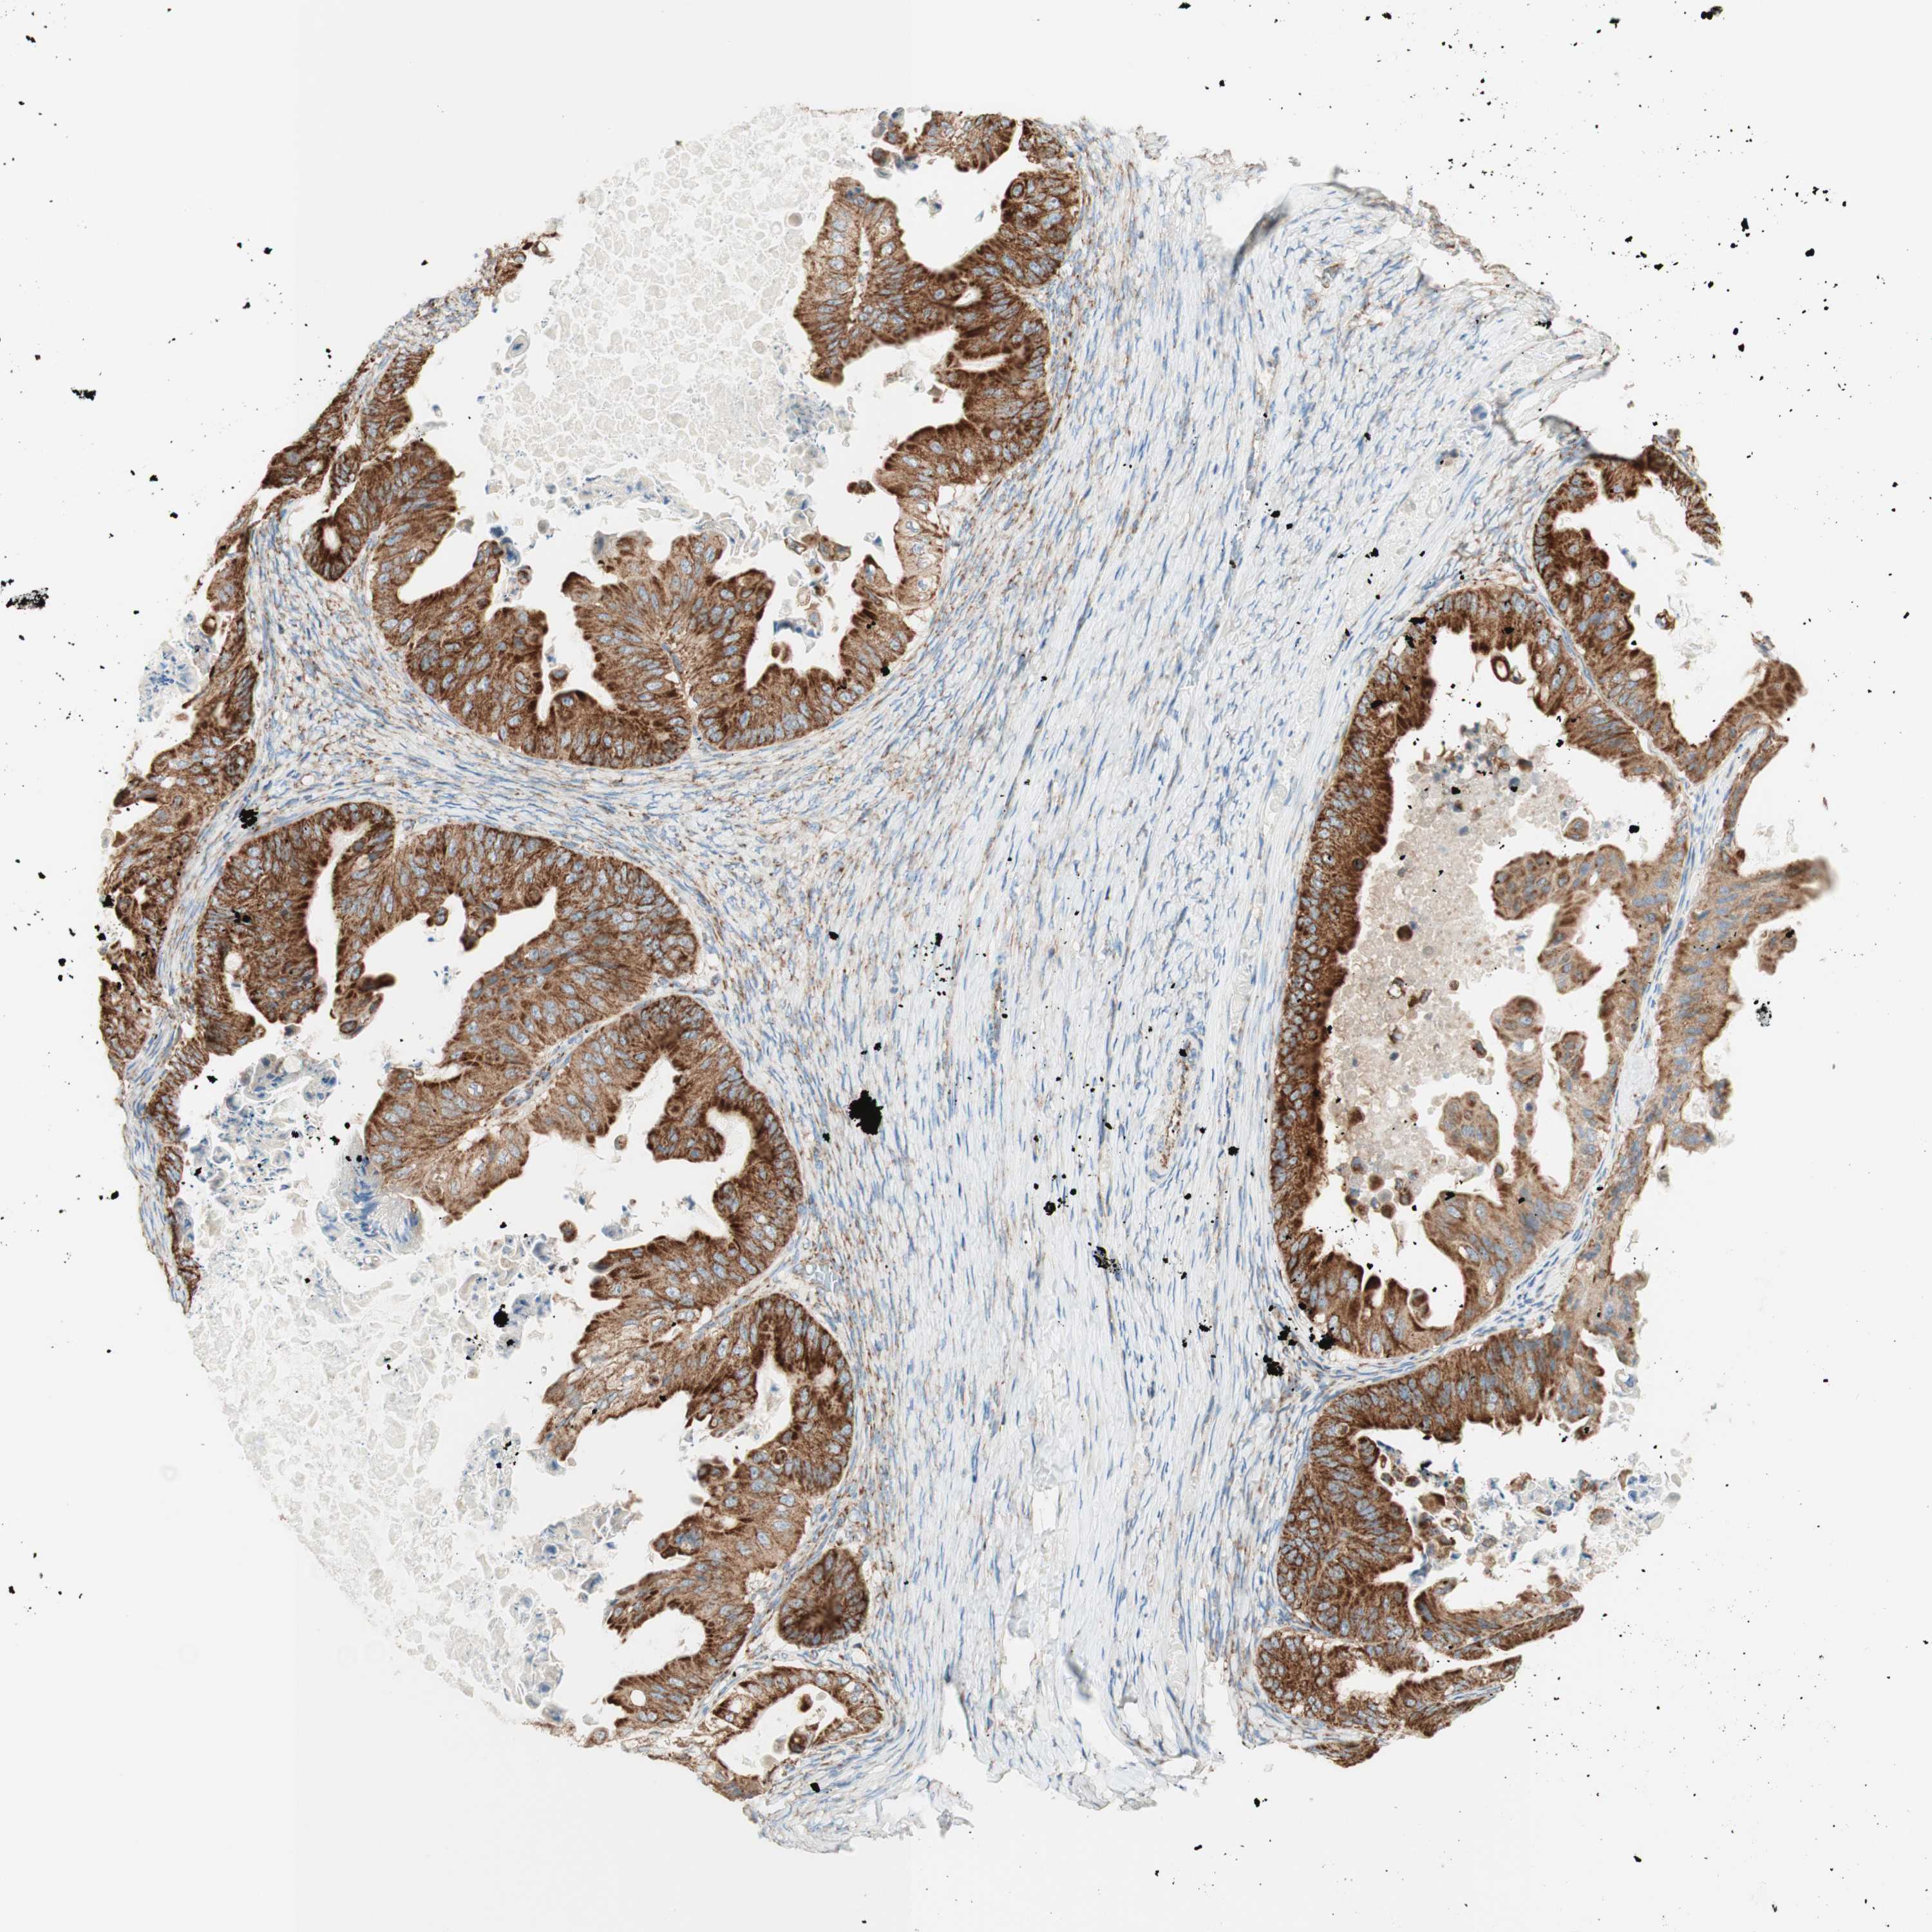

OVARIAN CANCER - Protein expressioni

A mouse-over function shows sample information and annotation data. Click on an image to view it in a full screen mode. Samples can be filtered based on level of antibody staining by selecting one or several of the following categories: high, medium, low and not detected. The assay and annotation is described here.

Note that samples used for immunohistochemistry by the Human Protein Atlas do not correspond to samples in the TCGA dataset.

Antibody stainingi

Antibody staining in the annotated cell types in the current human tissue is reported as not detected, low, medium, or high, based on conventional immunohistochemistry profiling in selected tissues. This score is based on the combination of the staining intensity and fraction of stained cells.

Each image is clickable and will lead to virtual microscopy that enables deeper exploration of all samples and also displays staining intensity scores, fraction scores and subcellular localization as well as patient and tissue information for each sample.

Antibody HPA011562

Antibody CAB005585

Staining

High

Cystadenocarcinoma, serous, NOS

Carcinoma, endometroid

Cystadenocarcinoma, mucinous, NOS

Carcinoma, NOS